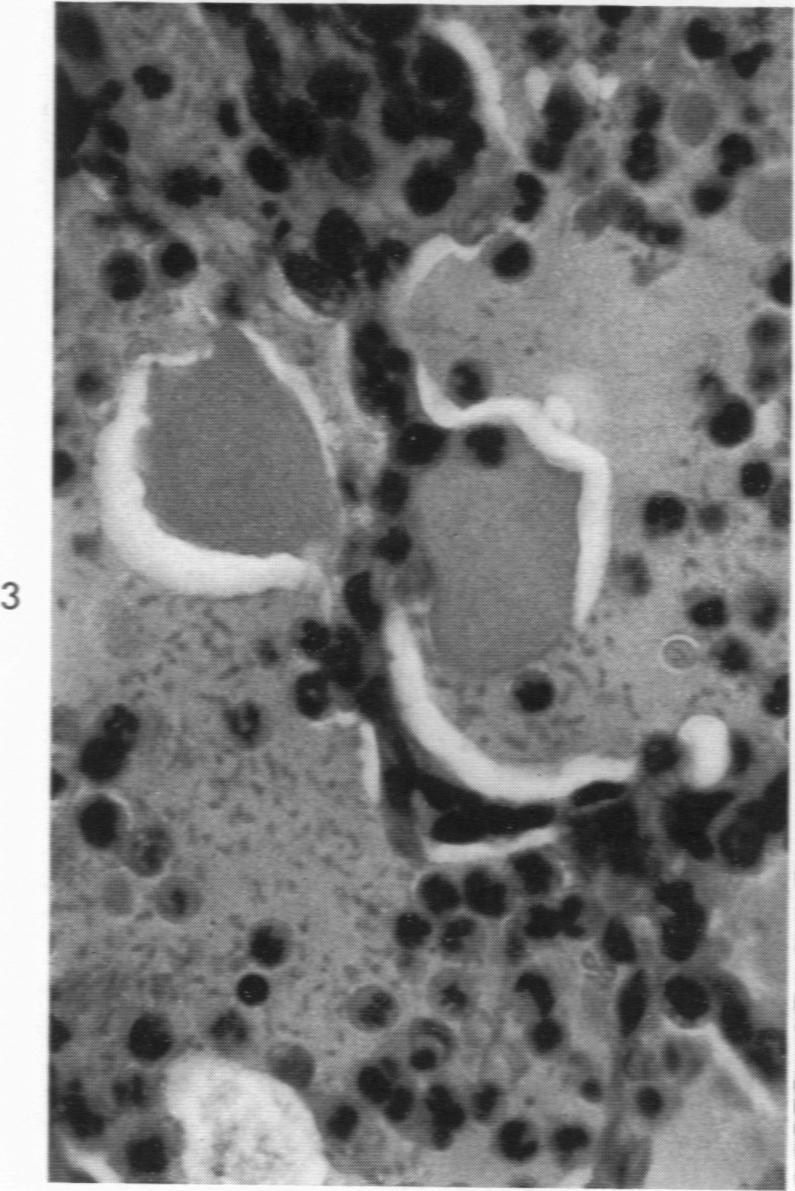

Pneumonic plague in monkeys. An electron microscopic study.

Am J Pathol. 1969 Feb;54(2):167-85.